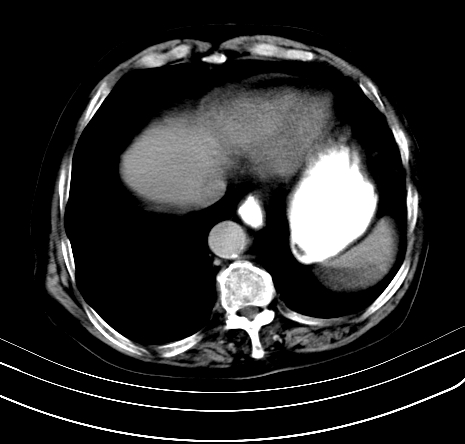

上腹部疼痛不适,行ct检查

胰腺明显肿大,密度减低,考虑慢性胰腺炎,假性囊肿形成不除外。

胰腺明显肿大,考虑慢性胰腺炎假性囊肿形成,不除外胰腺癌可能。

胰腺较明显扩大,胰周有渗出;肾周筋膜有增厚渗出,以左肾为著。应考虑急性胰腺炎。